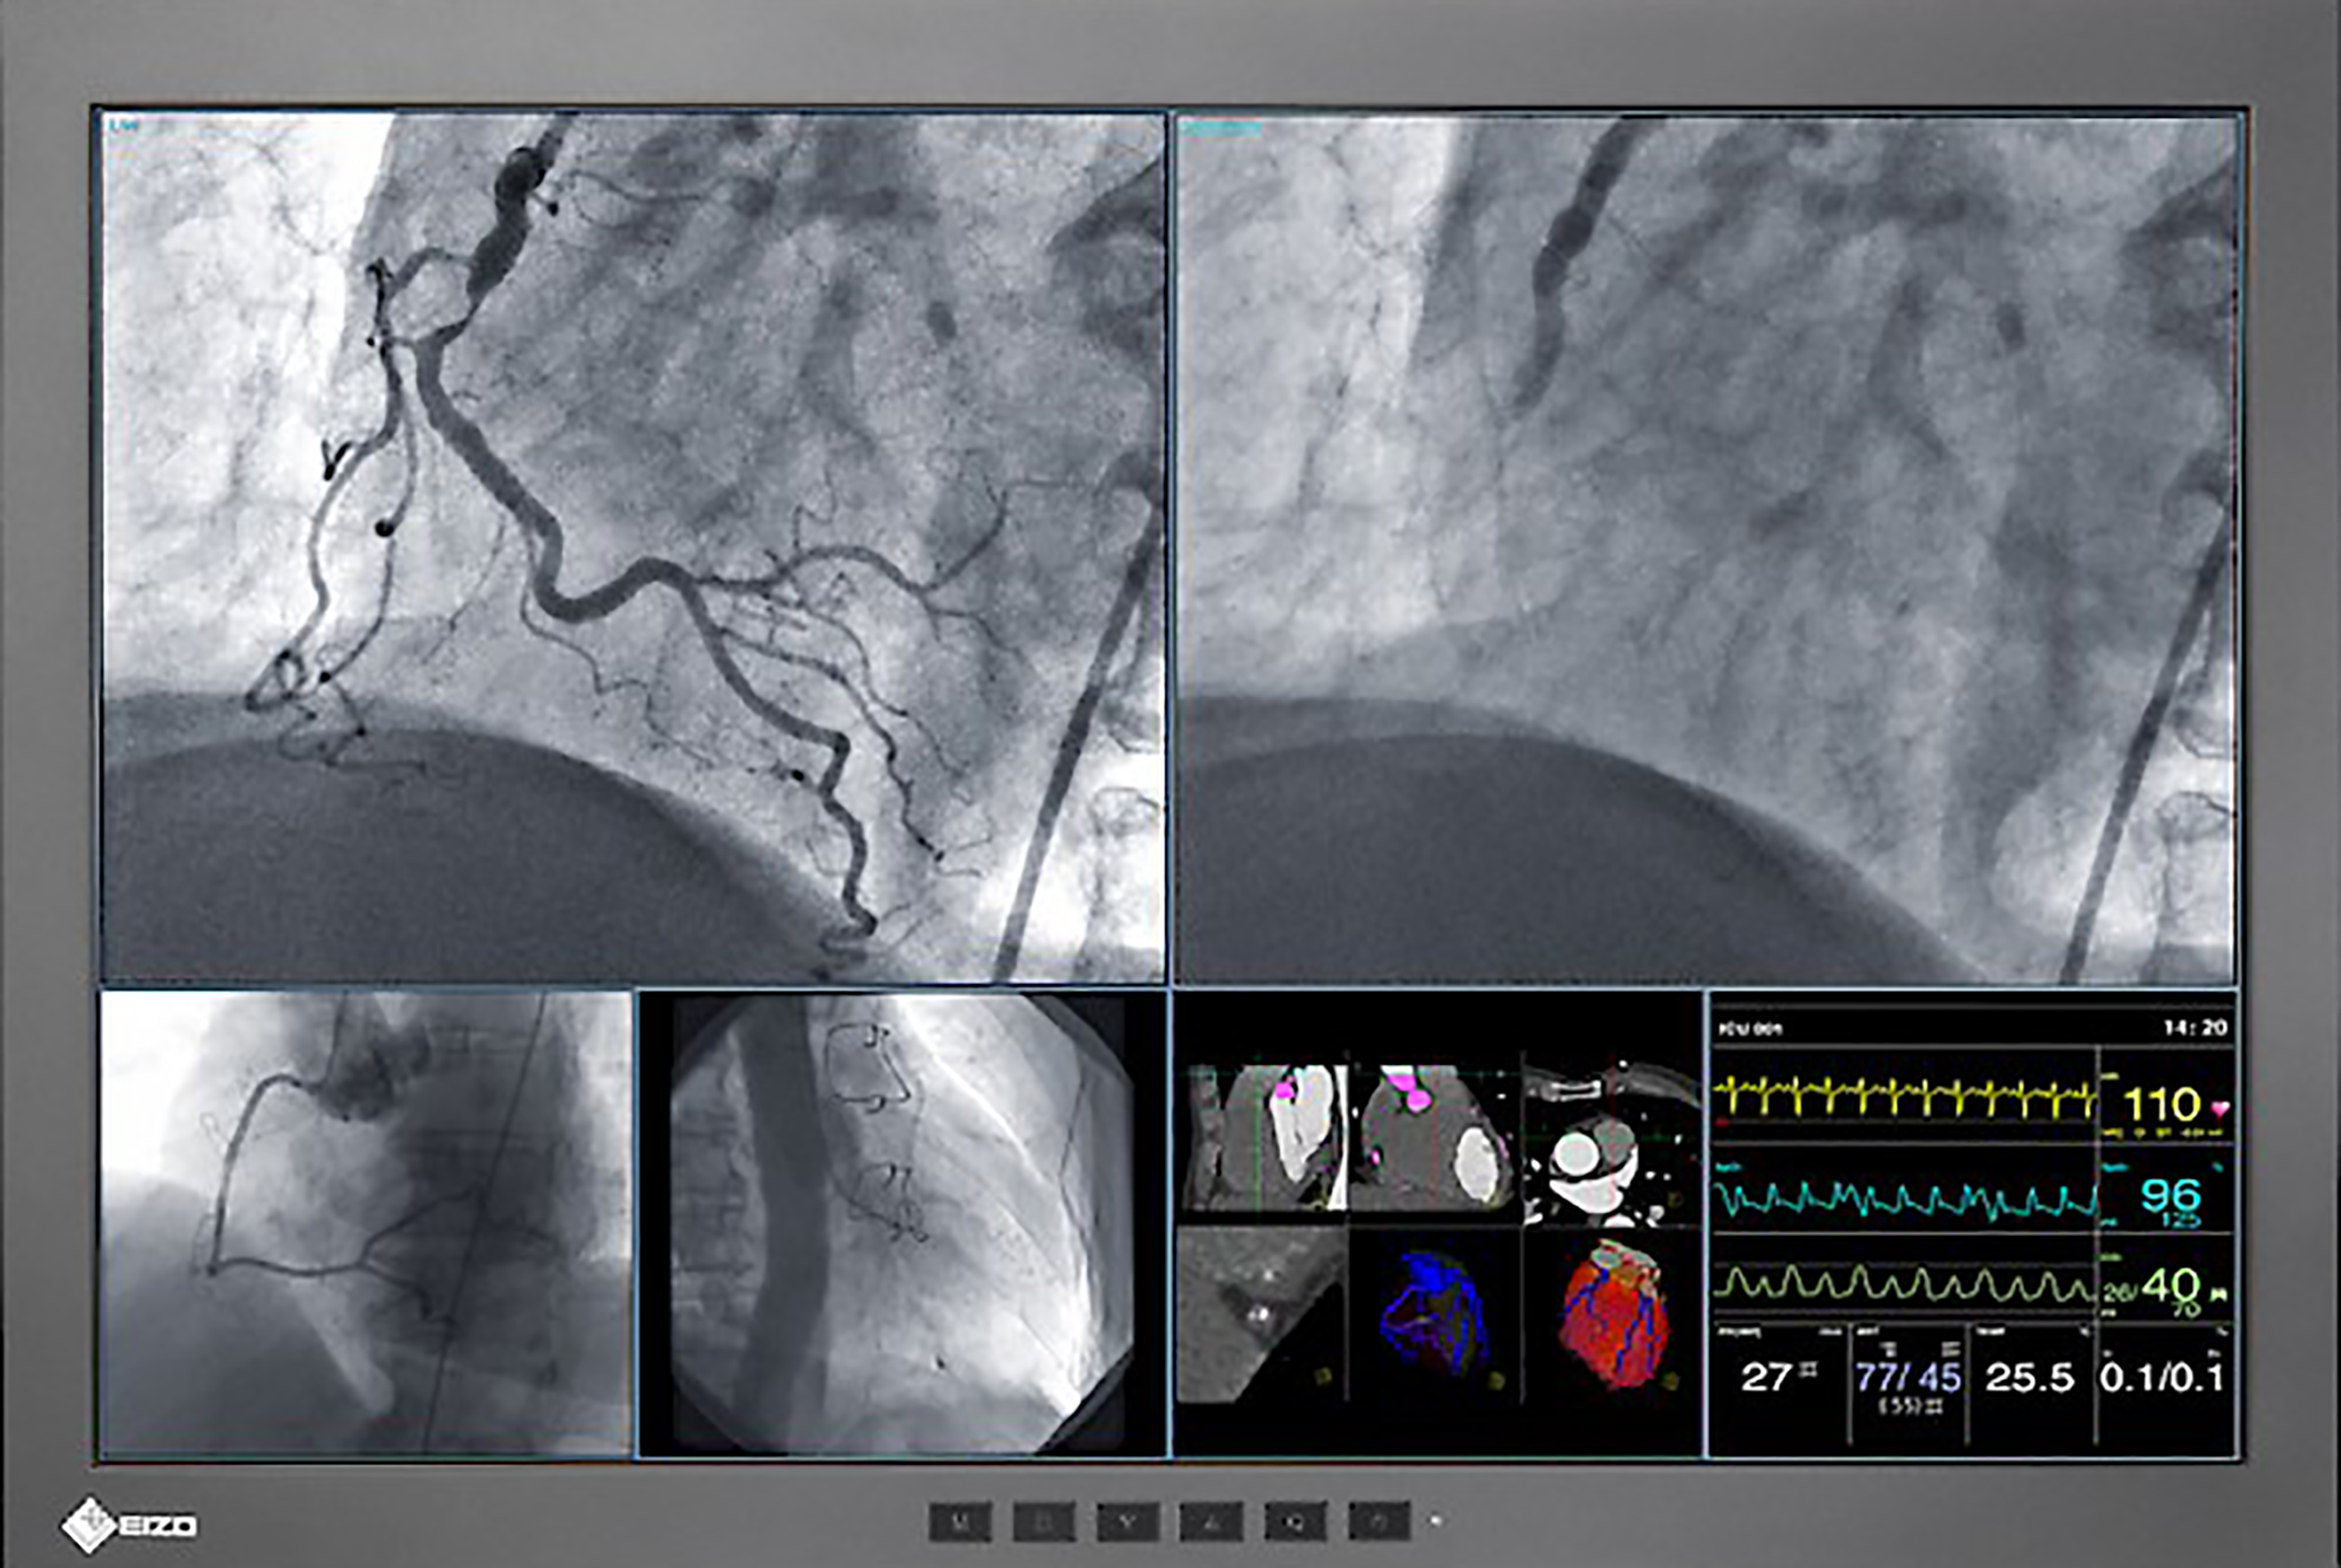

CuratOR EX190

SCD 19102